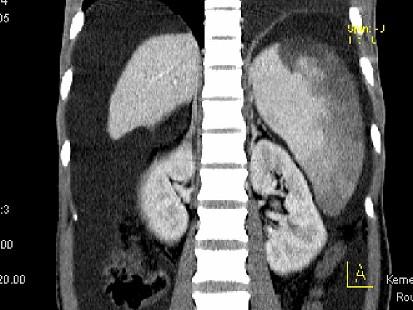

问题 患者男,29岁,乙肝病史10余年,腹胀,有移动性浊音,影像检查如图,最全面的诊断是 ( )

选项 A、大网膜膈下间位及脾梗 B、胆结石及脾梗 C、肝硬化腹水 D、肝硬化腹水、脾梗、胆囊结石 E、肝硬化

答案 D